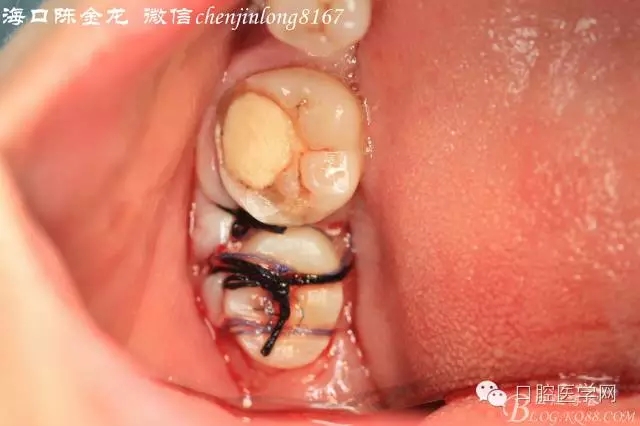

拔牙窩預(yù)備移植后,縫合固定